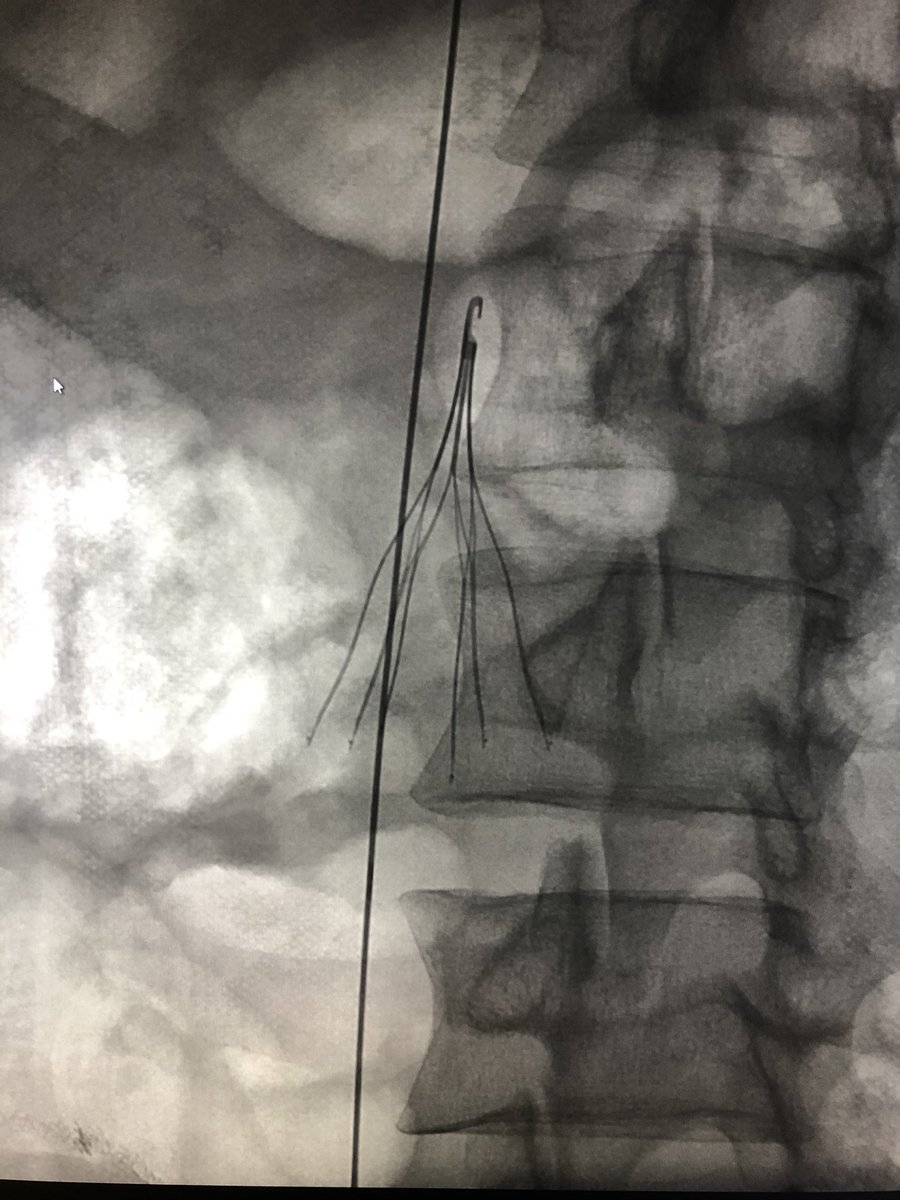

Option Elite filter in since February 2021 initially failed loop snare and forceps techniques, taken out with @PhilipsHealth #CavaClear laser sheath. 9 seconds of laser time. Great experience! #filterout @IrColorado @pj_rochon